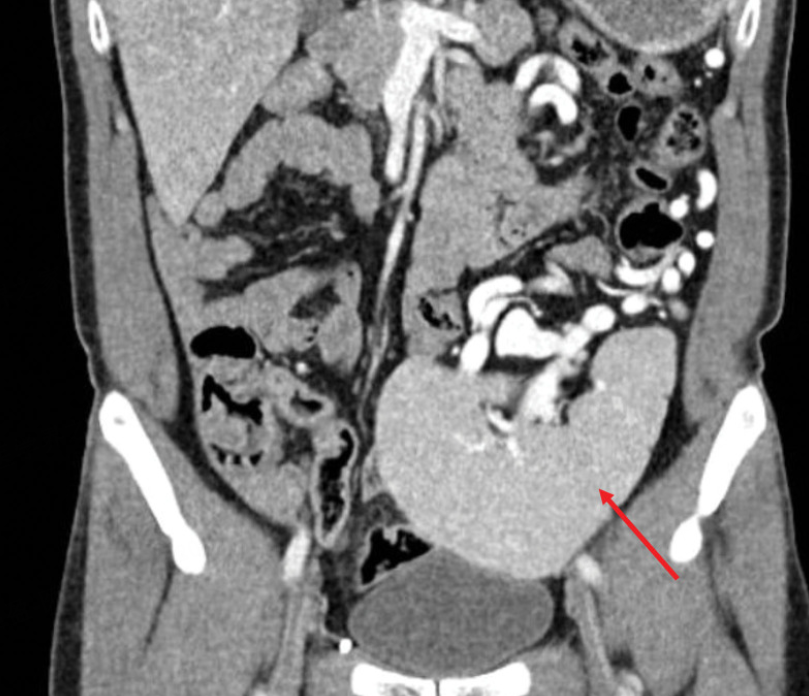

腹部CT检查显示:

图2 患者腹部CT检查结果

老周的脾脏并没有老老实实待在左上腹,而是“掉”到了盆腔里!同时,脾静脉明显增粗,胃周围能看到大量因为压力过高而生成的侧枝血管。尽管患者有大量饮酒史,影像学上未发现肝硬化或门静脉扩张的证据。